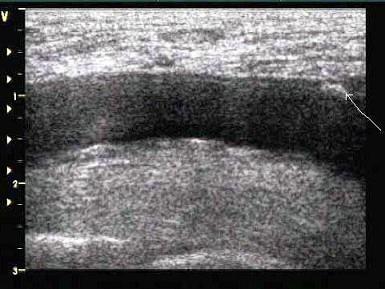

某患者颈部动脉声像图,根据箭头所示处是?(?)A.粥样斑块B.血栓C.动脉瘤D.以上都不是E.夹层动脉瘤

问题 某患者颈部动脉声像图,根据箭头所示处是?(?)

选项 A.粥样斑块 B.血栓 C.动脉瘤 D.以上都不是 E.夹层动脉瘤

答案 A